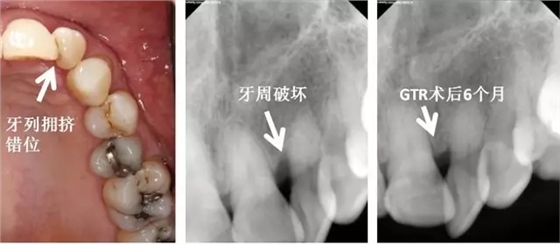

左上側(cè)切牙扭轉(zhuǎn),牙列擁擠,造成口腔衛(wèi)生困難,牙周破壞。告知患者牙列擁擠應(yīng)該予以治療以去除危險(xiǎn)因子,再進(jìn)行牙周手術(shù)?;颊卟辉敢庹委?,選擇直接牙周手術(shù)。告知患者需要高質(zhì)量口腔衛(wèi)生,并且需要更為頻繁的專(zhuān)業(yè)清潔。